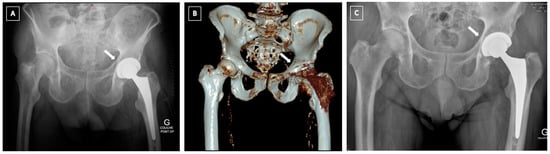

4.3. Pelvic Discontinuity (PD)

- The “Cup-cage construct” technique, currently the most popular treatment of chronic PD [42], was first described by Hanssen and Lewallen in 2005 [44]. It consists of an ilio-ischial cage, placed over an uncemented highly porous metal cup. In a majority of the cases, “jumbo cups”, defined by von Roth et al. [45] as an acetabular component with an outside diameter ≥66 mm in men and ≥62 mm in women, are used and thus help restore the centre of rotation (COR) of the hip in an anatomic position [46,47]. Remaining bone defects can be filled with augments or allograft. The cage offers initial stability and allows the osteointegration of the acetabular component. A polyethylene liner is then cemented in the cage in the correct position. Advantages of this technique are its favourable outcomes and high survival rates, ranging from 75–100% [37,42,48,49,50,51,52]. The main complications of this technique are dislocation (7–8%), infection (4–7%) and aseptic loosening (4–15%) [37,42,48,49].